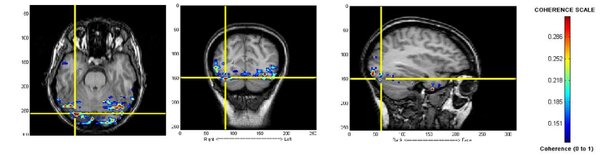

Functional Network Connectivity: Possible Biomarker for Autism Spectrum Disorders (ASD)

Wang et al. | Feb 23, 2015

Autism spectrum disorder (ASD) is a complex neurodevelopmental disorder and is difficult to diagnose in young children. Here magnetoencephalography was used to compare the brain activity in patients with ASD to patients in a control group. The results show that patients with ASD have a high level of activity in different areas of the brain than those in the control group.